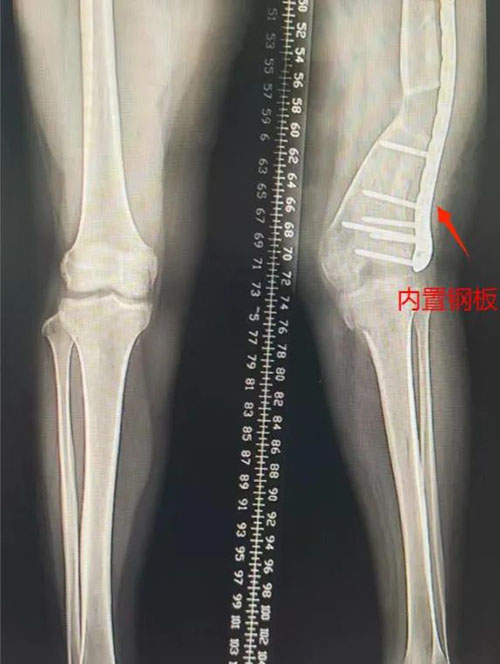

第二步:经过第一步的治疗,左下肢外翻畸形基本纠正,力线恢复,尽早拆除Illizarov架,予行切开钢板内固定术。

▲术前畸形,拆除外固定架,钢板内固定

术后半年,力线恢复